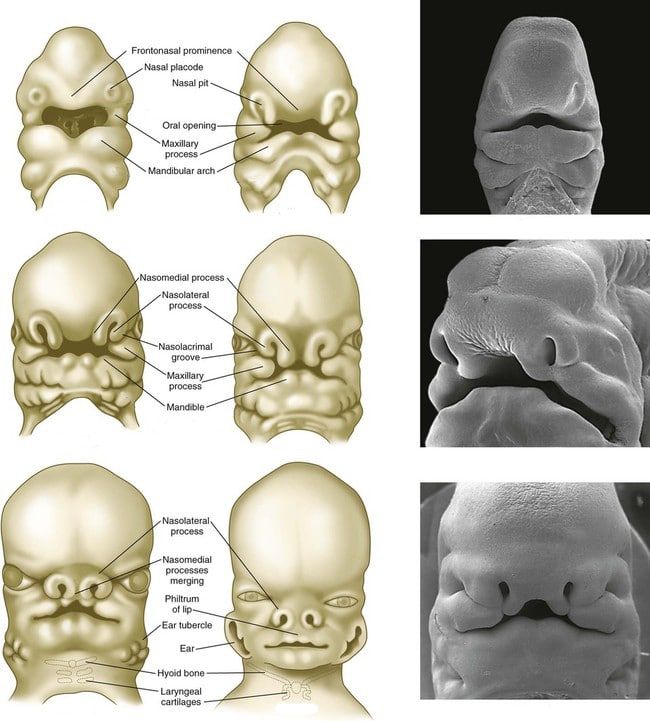

Co mówi nam anatomia i embriologia?

To co widzicie najłatwiej będzie wyjaśnić przemycając szybką lekcję anatomii i embriologii. W miarę rozwoju naszych twarzy, formuje się seria wyrostków (processes) (nosowe, szczękowe i żuchwowe), które łączą się w linii środkowej, tworząc ciągłą centralną strukturę, której pozostałością są guzki.

Źródło: https://teachmeanatomy.info/the-basics/embryology/head-neck/face-palate/

Źródło: https://teachmeanatomy.info/the-basics/embryology/head-neck/face-palate/

U niektórych osób miejsce połączenia się guzków nie jest widoczne, jednak u innych może być bardzo wyraźne.